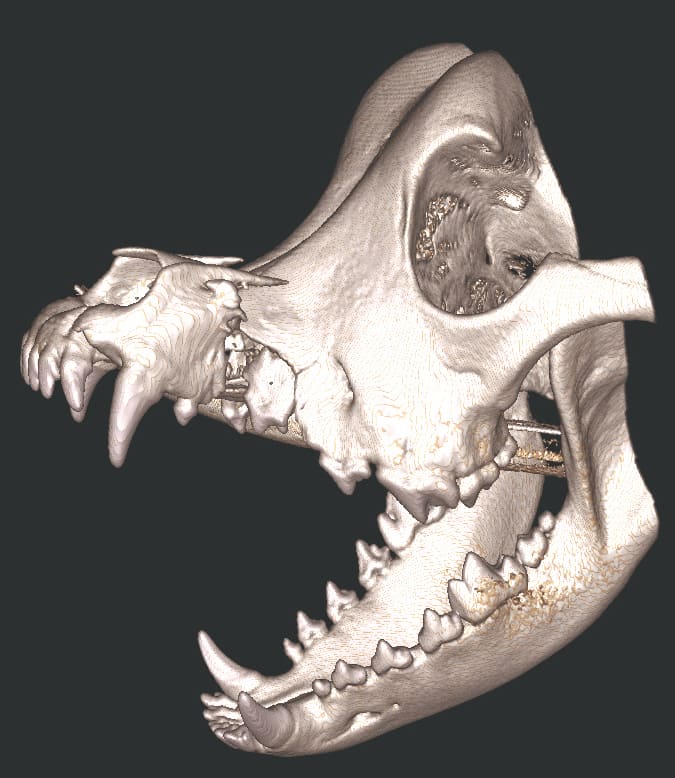

Cone Beam Computed Tomography

The Center now provides advanced imaging via cone beam CT. Cone beam CT is excellent for visualization of bony structures of the skull, nasal cavity, teeth, and ears. Cone beam CT is especially helpful for diagnosing dental disease and evaluation of jaw fractures. It can also be useful for evaluating the sinuses and tympanic bulla. Cone beam CT can be used in conjunction with nasal biopsy and culture to evaluate nasal discharge whether chronic or acute.

Repair of Maxillofacial Fracture

Pets can be involved in trauma that can cause fractures to their head, teeth, and jaw bones. Correctly repairing these fractures is extremely important for your pet to have normal function of their mouth. If a jaw fracture is allowed to heal in an abnormal position, your pet may have great difficulty chewing and can be in significant pain. Many fractures can be successfully treated with minimally invasive oral procedures, but more complicated cases may require bone plating techniques. The Center offers cone beam CT imaging which provides extremely detailed images of the bones of the head and skull. Advanced imaging with CBCT facilitates selection of the best surgical technique to get your pet back to eating and comfort as soon as possible.